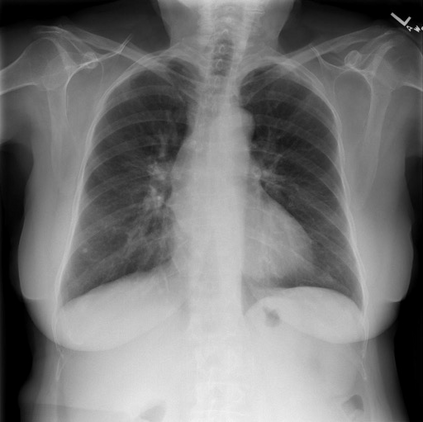

To address these issues, we propose a novel Adaptive patch-word Matching (AdaMatch) model to correlate chest X-ray (CXR) image regions with words in medical reports and apply it to CXR-report generation to provide explainability for the generation process. AdaMatch exploits the fine-grained relation between adaptive patches and words to provide explanations of specific image regions with corresponding words. To capture the abnormal regions of varying sizes and positions, we introduce the Adaptive Patch extraction (AdaPatch) module to acquire the adaptive patches for these regions adaptively. In order to provide explicit explainability for CXR-report generation task, we propose an AdaMatch-based bidirectional large language model for Cyclic CXR-report generation (AdaMatch-Cyclic). It employs the AdaMatch to obtain the keywords for CXR images and `keypatches' for medical reports as hints to guide CXR-report generation. Extensive experiments on two publicly available CXR datasets prove the effectiveness of our method and its superior performance to existing methods.